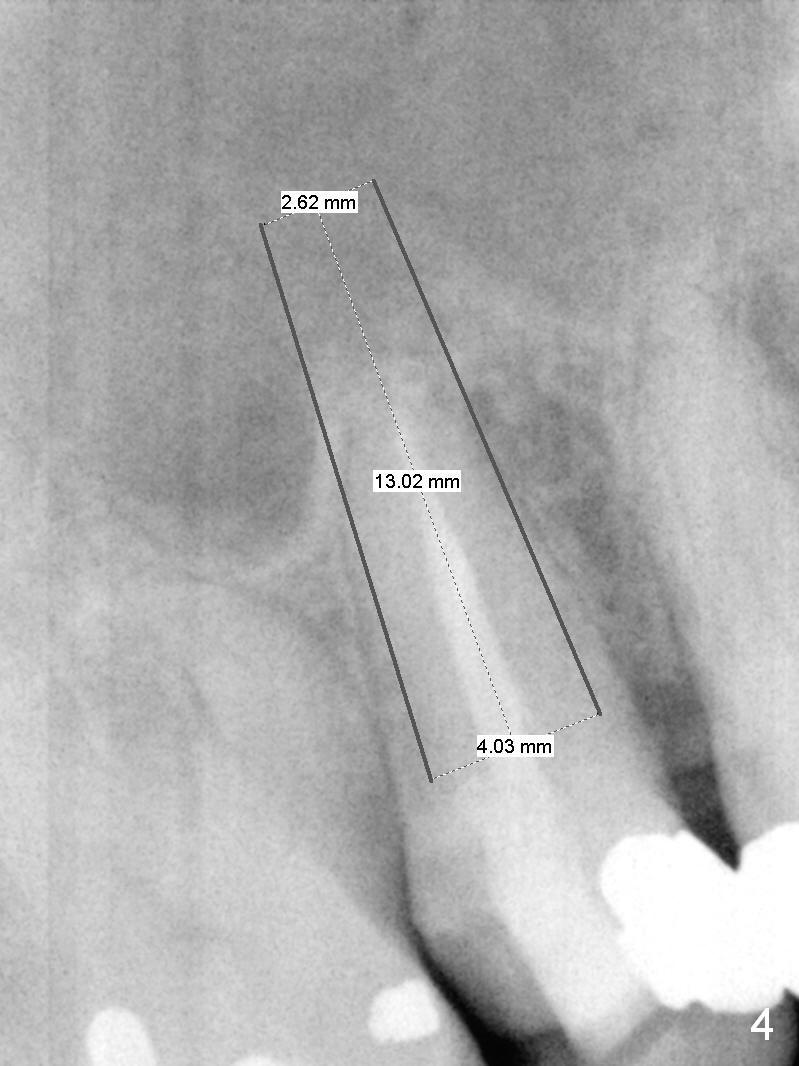

A 55-year-old man had 2nd caries with pulpitis at the tooth #4 a year ago (Fig.1), requiring RCT (Fig.2). The tooth fractured biting on a piece of nut shell inside a moon cake recently (Fig.3 *, 5, 6). There is a sinus septum apical to the apex of the affected tooth (Fig.1-3 arrowheads). After extraction and Metronidazole socket treatment, an immediate implant can be inserted into the septum for primary stability (Fig.4). The diameter of the implant will be decided by the measurement of the mesiodistal width of the root. Magic Expander (ME 3.0 mm) will be used to initiate osteotomy by going deep 4 mm, followed by ME 3.3 mm). If there is resistance to the 1st ME, use 1.6 mm drill. Allograft will be pushed upward with ME 3.3 mm prior to implant placement. Or try to insert (without tapping) ME 4.8 mm as deep as possible, hopefully with stability, and take PA. Place a larger implant for primary stability (4.5x11 mm).